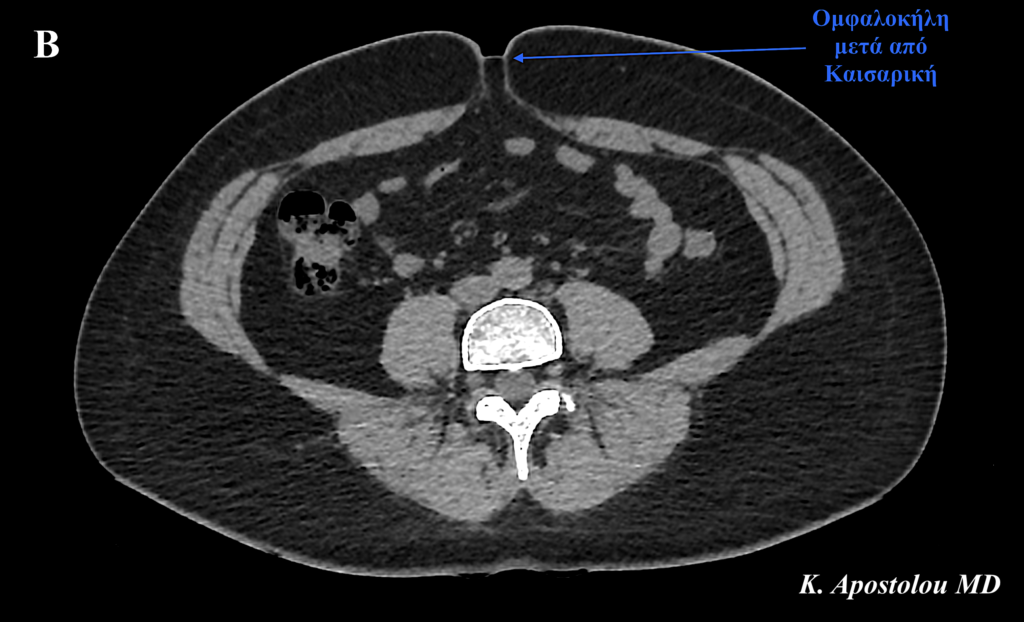

Η κλινική εξέταση της ασθενούς πραγματοποιήθηκε με την ασθενή τόσο σε ύπτια θέση όσο και σε όρθια στάση του σώματος, αποκαλύπτοντας:

- Κήλη μετά από καισαρική τομή, με σύγχρονη

- Ομφαλοκήλη μετά από καισαρική.

Η κλινική διάγνωση επιβεβαιώθηκε με την πραγματοποίηση αξονικής τομογραφίας άνω και κάτω κοιλίας, η οποία ανέδειξε την παρουσία μίας κήλης στην καισαρική τομή διαστάσεων 6.5 x 2.5 cm καθώς και μίας σύγχρονης ομφαλοκήλης διαστάσεων 1.9 x 1.4 cm.